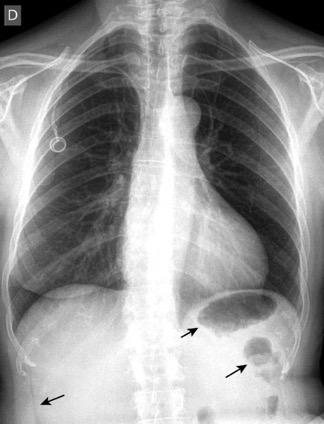

Ascitis. Masa abdominal

Hepatoesplenomegalia

Riñones poliquísticos

Distensión abdominal.

Reeder-Felson. Gamuts in Radiology.2017

Hepatomegalia metastática. Ca. de pulmón

Ascitis masiva

Carcinomatosis peritoneal

Elevación bilateral por riñones poliquísticos. Hernia hiatal ¡Sin gas en abdomen!